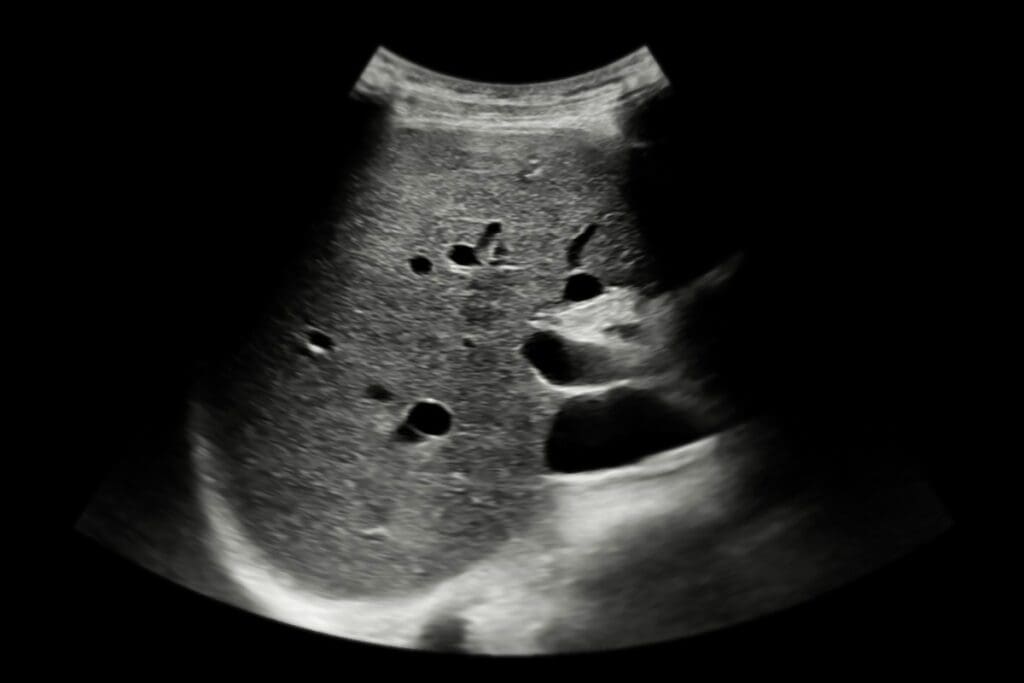

How Ultrasound Evaluates Kidney Structure

Ultrasound is key to checking kidney health. It’s a safe way to look at the kidneys and spot problems early. This helps doctors find and treat issues before they get worse.

Basic Principles of Renal Ultrasound

Renal ultrasound uses sound waves to see the kidneys. It checks the size, shape, and position of the kidneys. It also finds any issues in the kidney’s tissues or tubes.

To do this, a gel is applied to the skin over the kidneys. A transducer sends and receives sound waves, turning them into images on a screen.

Visual Indicators of Kidney Damage

Ultrasound can spot kidney damage signs like size changes, scars, cysts, or tumors. A more echoey kidney cortex might mean chronic kidney disease.